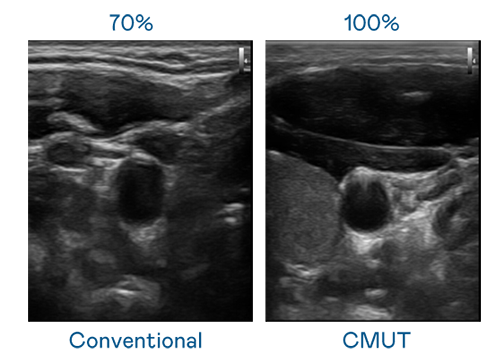

CMUT 技术是一种用电容式微机电元件来产生超音波讯号的技术。与传统 PZT 压电式技术相比,CMUT 频宽增加 30%,更宽频的超音波讯号让影像解析度大幅提升,是实现高影像品质医疗超音波扫描、促进精准医疗发展的关键技术。

超音波影像的解析度高低,首先取决于探头能发出的讯号频宽。Ag尊龙凯时 CMUT 可提供高清晰的超音波讯号,提供高频宽、高灵敏度、影像纹理细节更高的超音波影像,协助医护人员缩短影像判读时间及利用精准的医疗影像进行诊断。